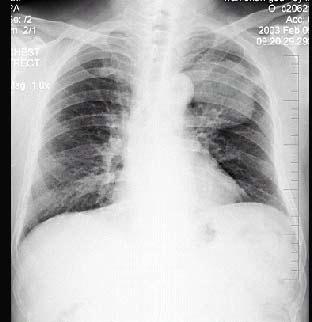

问题 男性,70岁,因胸痛就诊,不咳嗽、发热,X线检查如图,最可能的诊断是 ( )

选项 A.左肺结核瘤 B.左侧叶间积液 C.左肺癌 D.左肺炎性假瘤 E.支气管扩张

答案 C